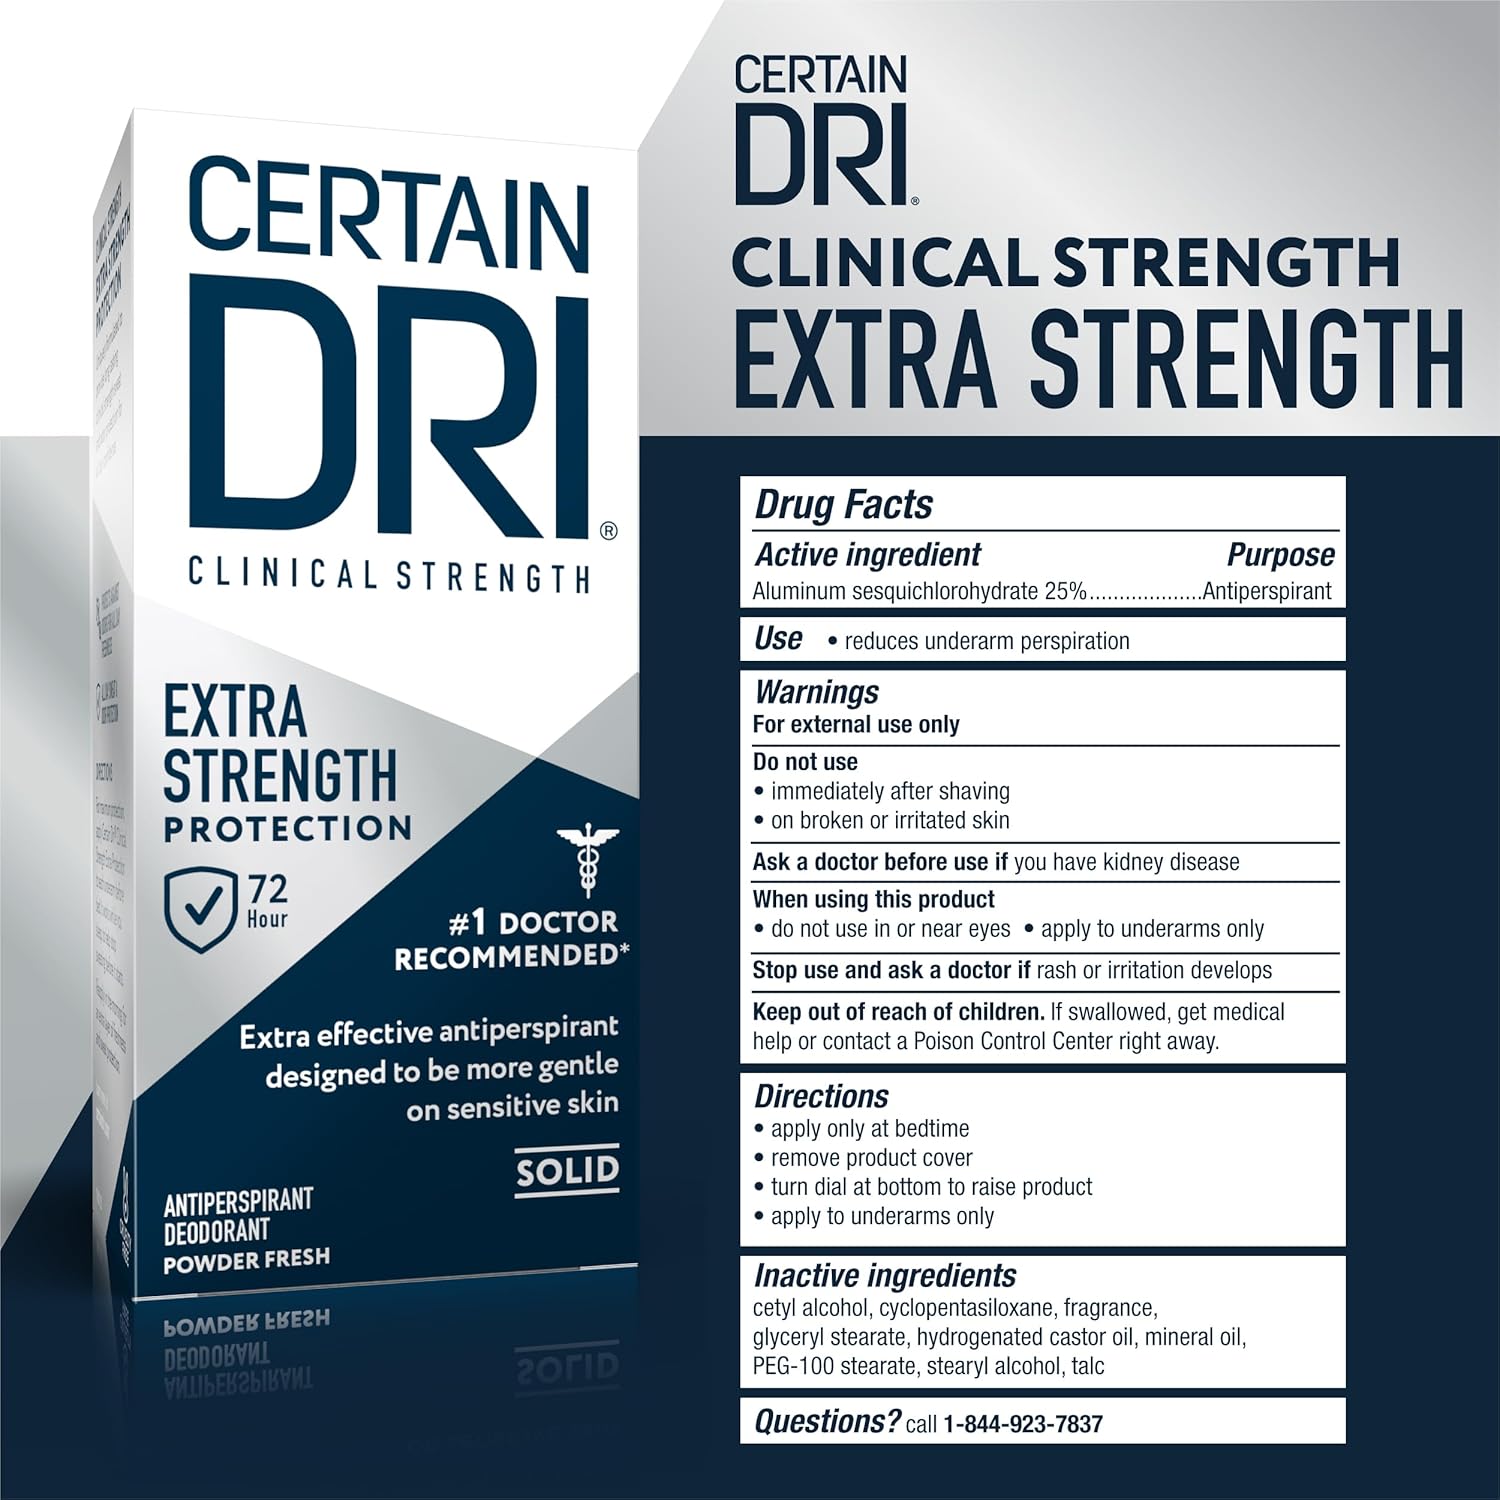

- CLINICAL STRENGTH PROTECTION: Extra-effective formula designed specifically for Hyperhidrosis and excessive sweating.

- 72-HOUR DEFENSE: Provides up to 3 days of reliable sweat and odor protection with a single application.

- DOCTOR RECOMMENDED: The #1 recommended over-the-counter antiperspirant brand by dermatologists.

- NIGHTTIME APPLICATION: Apply sparingly at bedtime to dry skin for best results; gentle on skin when used as directed.

- POWDER FRESH SCENT: Keeps you smelling clean and feeling confident without overpowering fragrance.

Regain your confidence with Certain Dri Extra Strength Clinical Solid Antiperspirant, the #1 doctor-recommended brand for excessive sweating. Specially formulated for Hyperhidrosis, this clinical-strength solid utilizes Aluminum Sesquichlorohydrate to deliver up to 72 hours of reliable sweat and odor protection. Unlike standard deodorants that merely mask wetness, Certain Dri targets the source of perspiration to keep you dry day and night. The gentle formula is designed to be applied sparingly at bedtime to completely dry skin, allowing the active ingredients to work while you sleep for maximum effectiveness. Wake up feeling protected and fresh, without the worry of sweat stains or body odor. This pack contains one 1.7 oz stick in a Powder Fresh scent.

Usage Note: To prevent irritation, apply only to completely dry skin before bed. Do not use immediately after showering, shaving, or on broken skin.